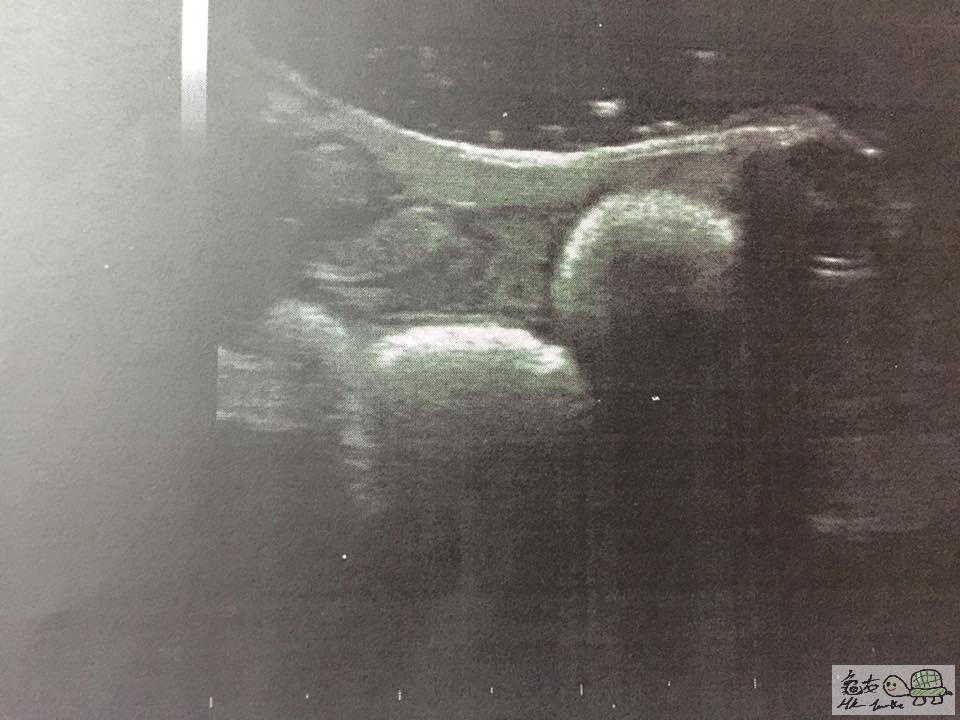

我諗之前間診所判錯症,宜家去左大圍某間獸醫睇,睇到佢有卵塞

月頭帶佢睇過第二個醫生,先去照左X光同抽血,做手術除切突出部份(唔洗好似上次咁要駁針~)

可以睇到有小小肺炎徵狀,需要每3日打一次抗生素

除左肺炎,醫生指佢開始有卵泡,日後如果無法排出就會有卵塞的情況,到時就要絕育!